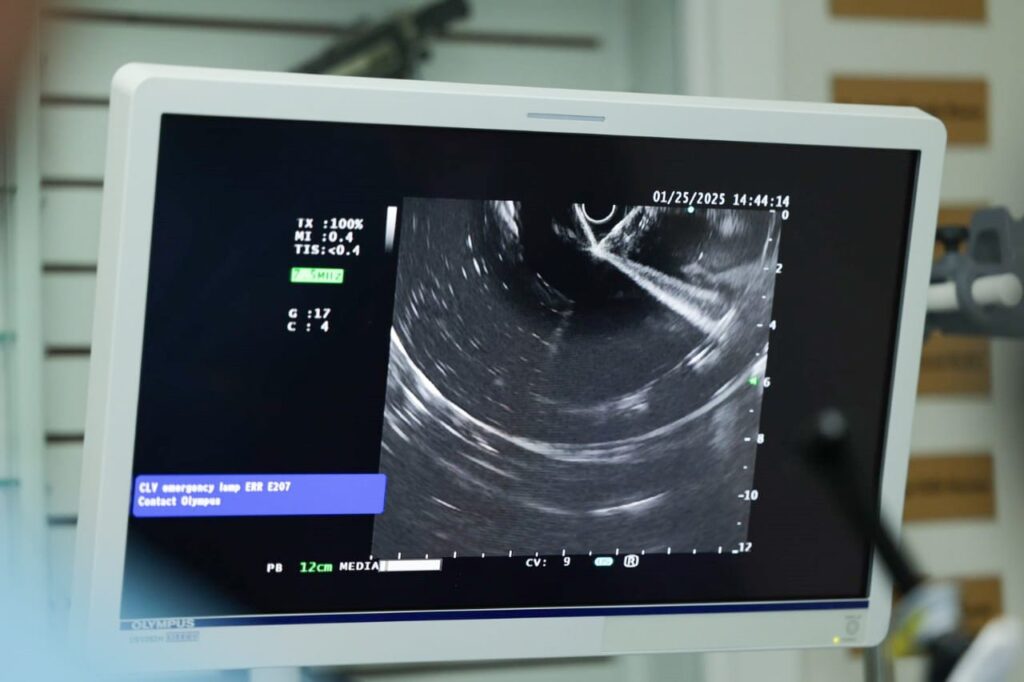

LIEEG 2025: Endoscopía de la Vía Biliar